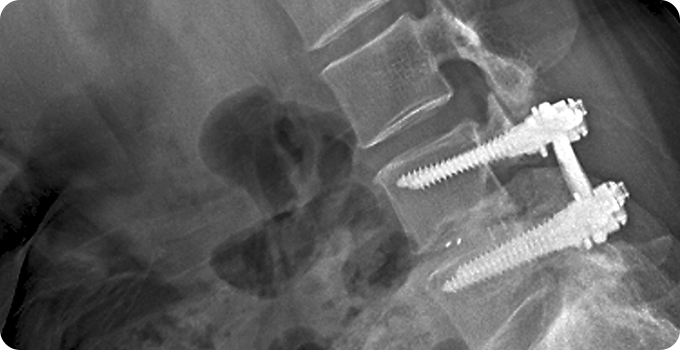

척추 고정술 사진

3

척추 고정술

척추가 불안정하거나 심하게 전위된 경우 사용하는 수술적 치료법입니다. 금속 나사나 막대를 이용해 손상된 척추를 고정하여 척추의 안정성을 회복하고 추가 손상을 방지합니다. 이 방법은 신경 압박을 해소하고 통증을 줄이는 데 효과적이며, 수술 후 재활과 관리를 통해 정상적인 척추 기능을 회복할 수 있습니다. 고정술은 전문의의 판단에 따라 최적의 치료법으로 선택됩니다.

• 직접적인

척추 고정

• 통증

완화

• 척추 안정성

회복

• 척추 기능